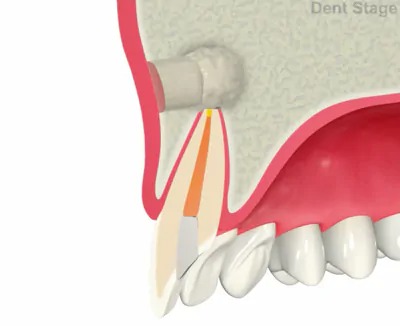

歯根端切除術

根管治療を行なっても症状が改善しない場合や根尖病巣が大きすぎて、根管治療では治せない場合等で行う施術方法です。歯茎を開いて、外科的な明視野で直接根尖病巣(歯根のう胞、歯根肉芽種)を取り除き、症状の改善を図ります。(※第一大臼歯までが適応です)

切開

骨の削除

炎症の除去

歯根の切断

薬剤充填

縫合